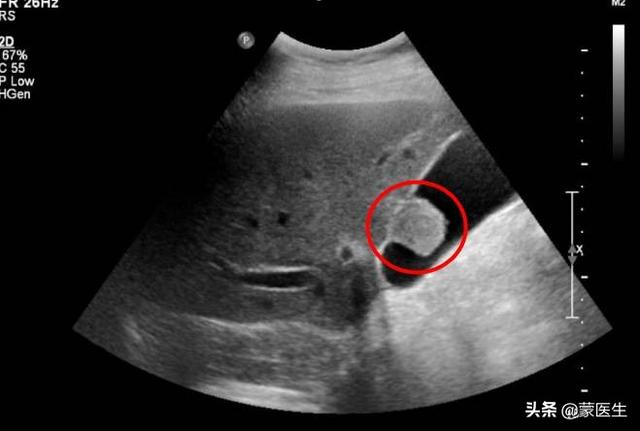

polype de la vésicule biliaire

Le cercle rouge est un polype de la vésicule biliaire.

Les polypes de la vésicule biliaire se divisent en vrais polypes et en faux polypes. Les faux polypes, également connus sous le nom de polypes de cholestérol, apparaissent volontiers en groupes, le diamètre de la plupart d'entre eux est inférieur à 1 cm, mais il n'y a que des cristaux de cholestérol, il n'y a donc pas de possibilité d'évolution maligne.

Les vrais polypes comprennent les adénomes de la vésicule biliaire, les adénomyomes, les polypes inflammatoires et l'hyperplasie adénomateuse. Les adénomes de la vésicule biliaire sont les plus dangereux, bien que l'incidence des polypes de la vésicule biliaire ne soit que d'environ 4 %, mais le taux de cancer est d'environ 20 à 30 %, ce qui explique qu'ils doivent généralement être combattus seuls.

Une échographie abdominale annuelle est recommandée pour les personnes âgées de plus de 40 ans. Les patients sans facteur de risque élevé, présentant des polypes de moins de 1 cm et âgés de moins de 50 ans devraient passer une échographie tous les 3 à 6 mois. Si les résultats restent bons, l'échographie peut être renouvelée une fois par an.